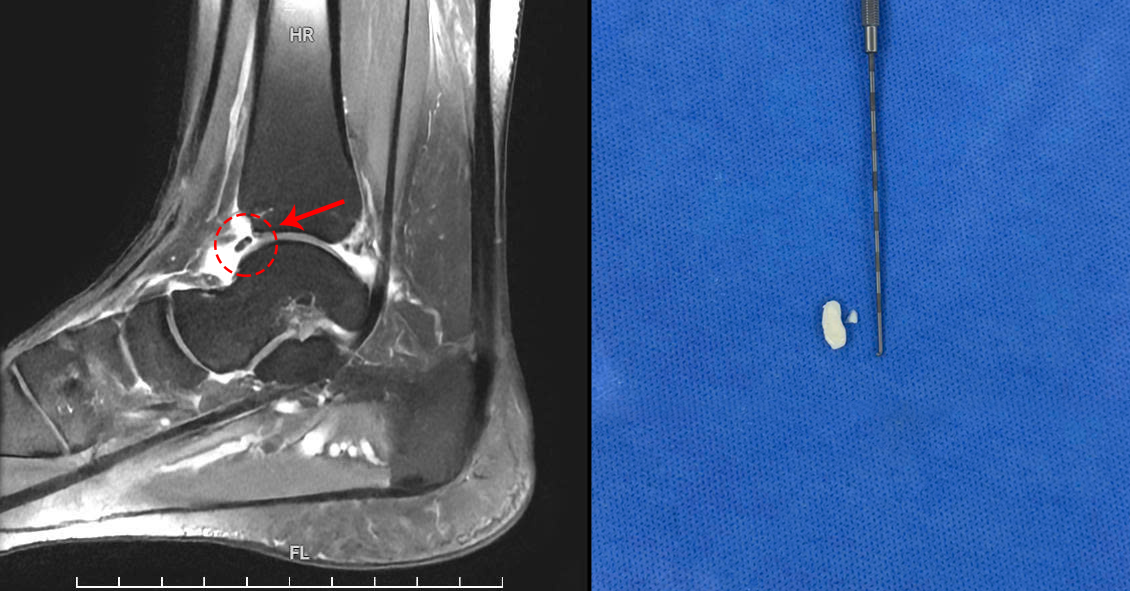

Loose bone and cartilage fragments in the patient's joint on an MRI scan (left) and after surgical removal (right). *Photo: Tam Anh General Hospital* |

Doctor of Medicine, Level II, Tran Tuan Anh, from the Orthopedic Trauma Department at Tam Anh General Hospital Hanoi, reported that ultrasound, X-ray, and MRI results revealed a mobile bone fragment measuring 3,6x1,6 mm. This fragment caused ankle impingement syndrome accompanied by synovitis of the ankle joint.

The doctor attributed the fragment to cartilage that detached when Huong fell from her vehicle a year prior, gradually calcifying. During her movements, this bone or cartilage piece would occasionally lodge between the joint space or ligaments, causing sharp pain. Over time, the foreign body would drift from its position, leading to Huong's pain spontaneously resolving and her ability to move normally. This random process meant that episodes of pain appeared and disappeared unpredictably, lasting one to two days or even a week; some months she experienced no pain, while others had multiple painful episodes. Recently, even a slight touch of her foot to the ground caused intense pain, making walking impossible.